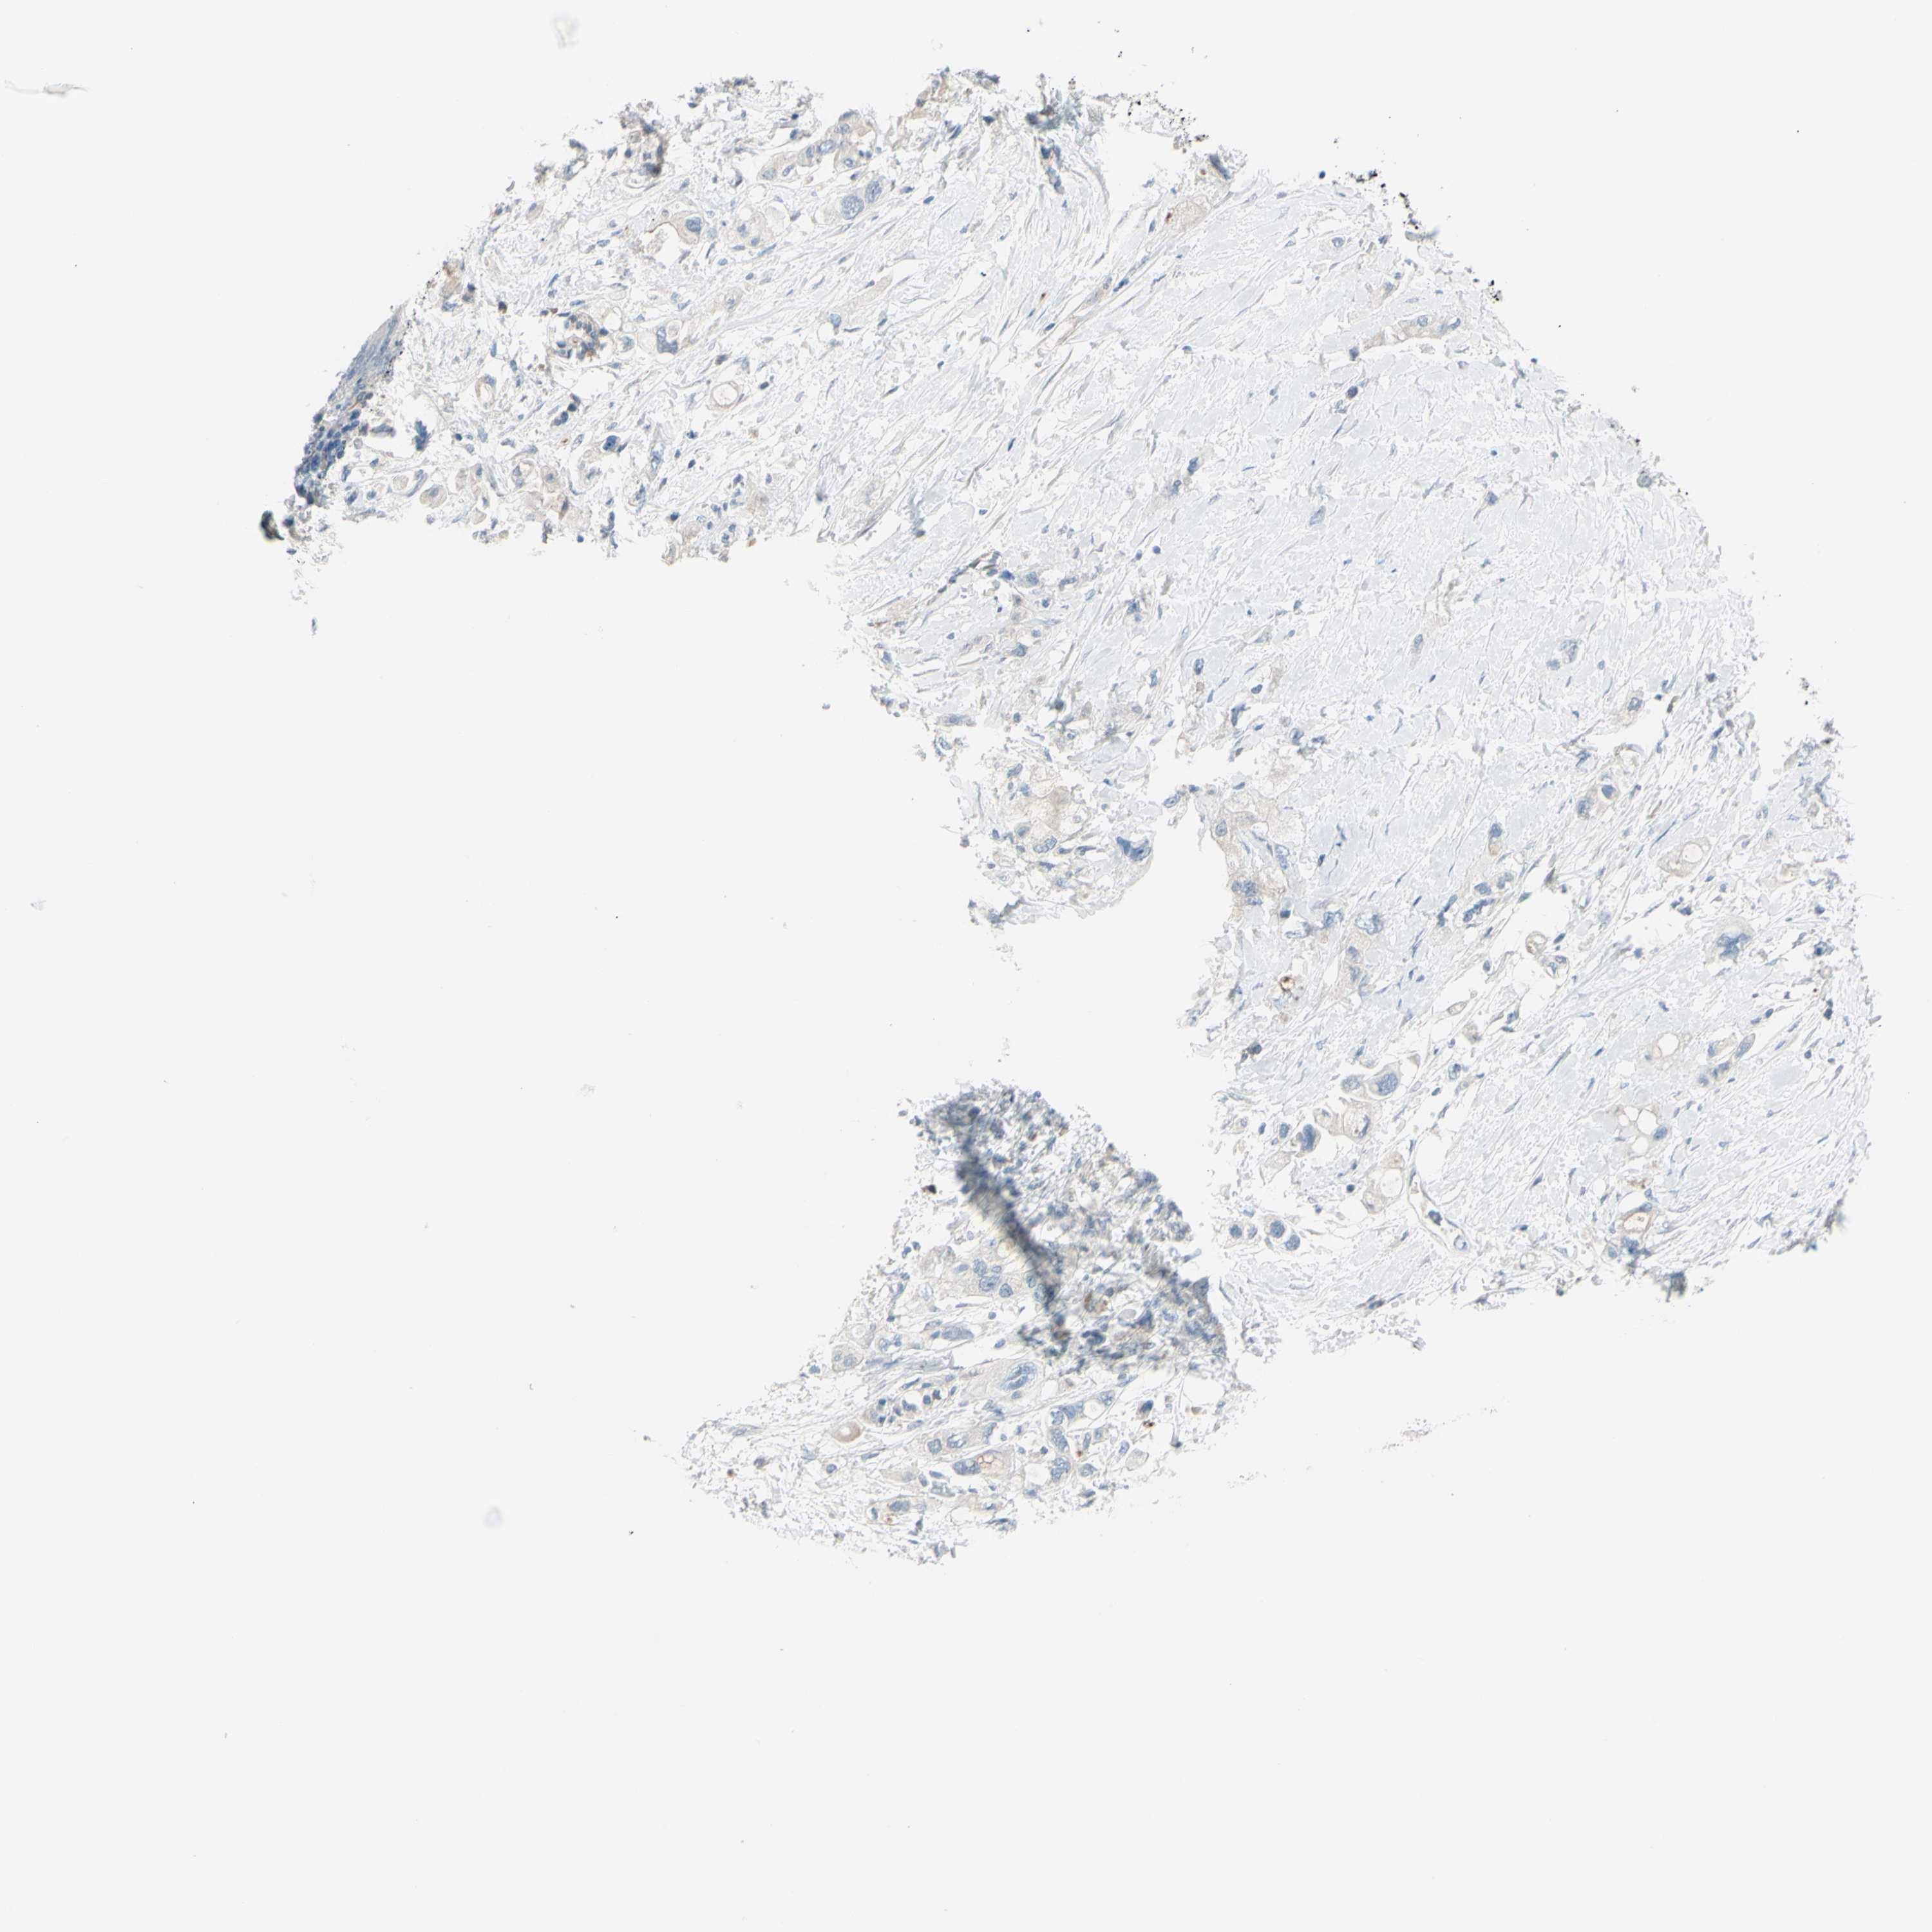

PANCREATIC CANCER - Protein expressioni

A mouse-over function shows sample information and annotation data. Click on an image to view it in a full screen mode. Samples can be filtered based on level of antibody staining by selecting one or several of the following categories: high, medium, low and not detected. The assay and annotation is described here.

Note that samples used for immunohistochemistry by the Human Protein Atlas do not correspond to samples in the TCGA dataset.

Antibody stainingi

Antibody staining in the annotated cell types in the current human tissue is reported as not detected, low, medium, or high, based on conventional immunohistochemistry profiling in selected tissues. This score is based on the combination of the staining intensity and fraction of stained cells.

Each image is clickable and will lead to virtual microscopy that enables deeper exploration of all samples and also displays staining intensity scores, fraction scores and subcellular localization as well as patient and tissue information for each sample.

Antibody HPA010668

Antibody CAB025490

Staining

High

Medium

Low

Not detected

Intensity

Strong

Moderate

Weak

Negative

Quantity

>75%

75%-25%

<25%

None

Location

Nuclear

Cytoplasmic/membranous

Cytoplasmic/membranous,nuclear

Adenocarcinoma, NOS

Adenocarcinoma, metastatic, NOS